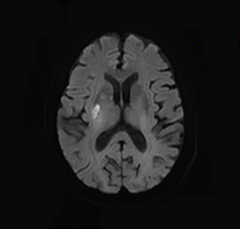

术后DWI:磁共振见少许新鲜脑梗死。

什么叫桡鞘【例久弥新】寻道于桡——瑞康通5.5F IntroSky X导管鞘经桡动脉行右侧大脑中动脉取栓一例_https://www.jmylbn.com_新闻资讯_第28张